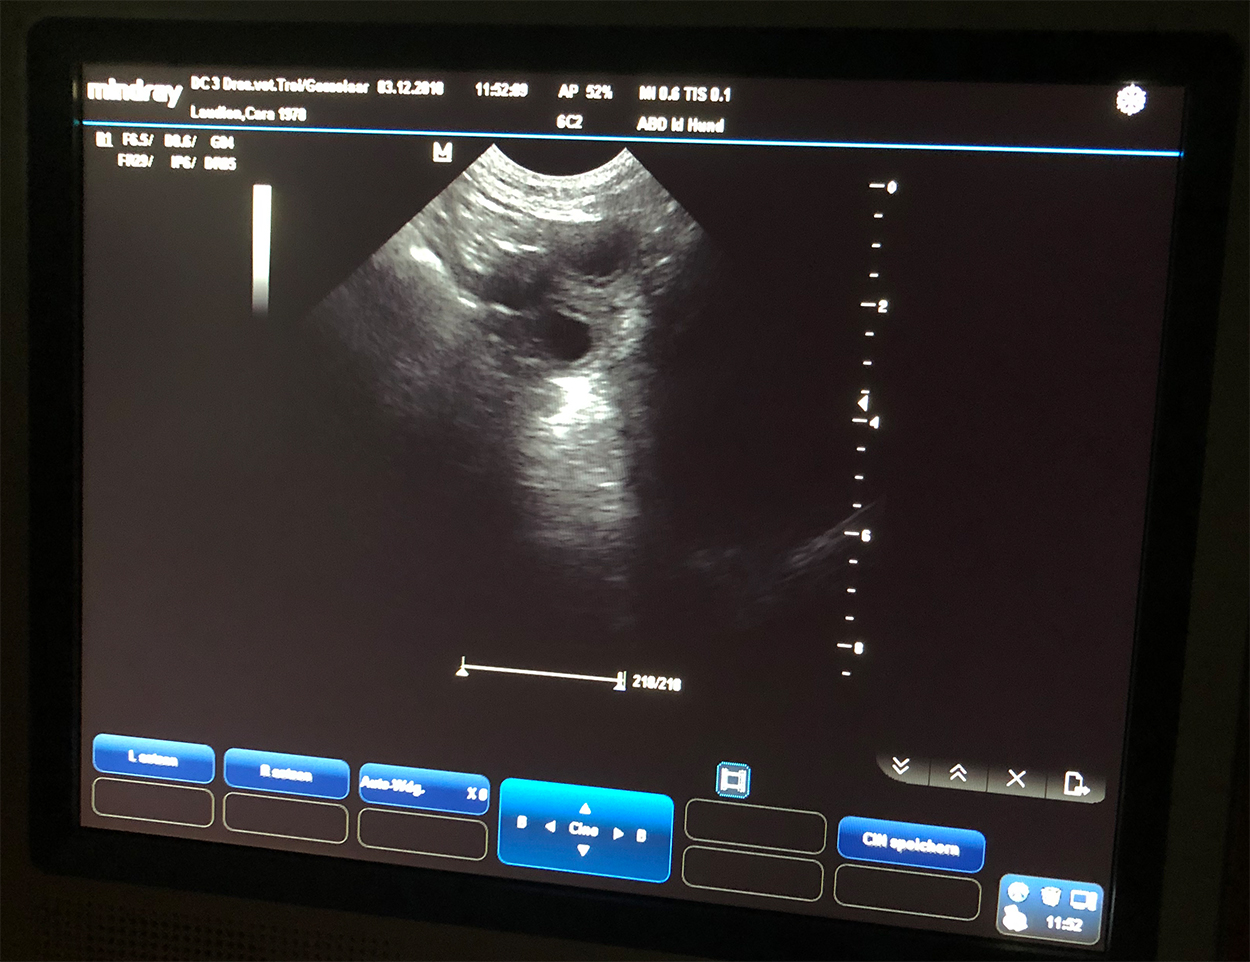

Am Montag war also der Tag der Tage. Der Tag an dem man Gewissheit bekommt, ob die Hündin aufgenommen hat oder nicht.

Auch wenn in den letzten Tagen einiges für eine Trächtigkeit gesprochen hat, so wollten wir es gerne

von unserer Tierärztin Heike Trei absegnen lassen. :-)

|

Beim Ultraschall wurden auf Anhieb einige Fruchtanlagen gesichtet. Die genaue Anzahl wollte ich aber nicht wissen.... ein bisschen Spannung soll uns und den Welpeninteressenten schon noch in den kommenden Wochen erhalten bleiben. ;-) |

Wir freuen uns einfach riesig darüber, dass bald wieder kleine H-Racker den Bagalutenhof besetzen werden.

Bis dato werden wir Cara weiterhin fit halten und auf unser Essen aufpassen. :-)